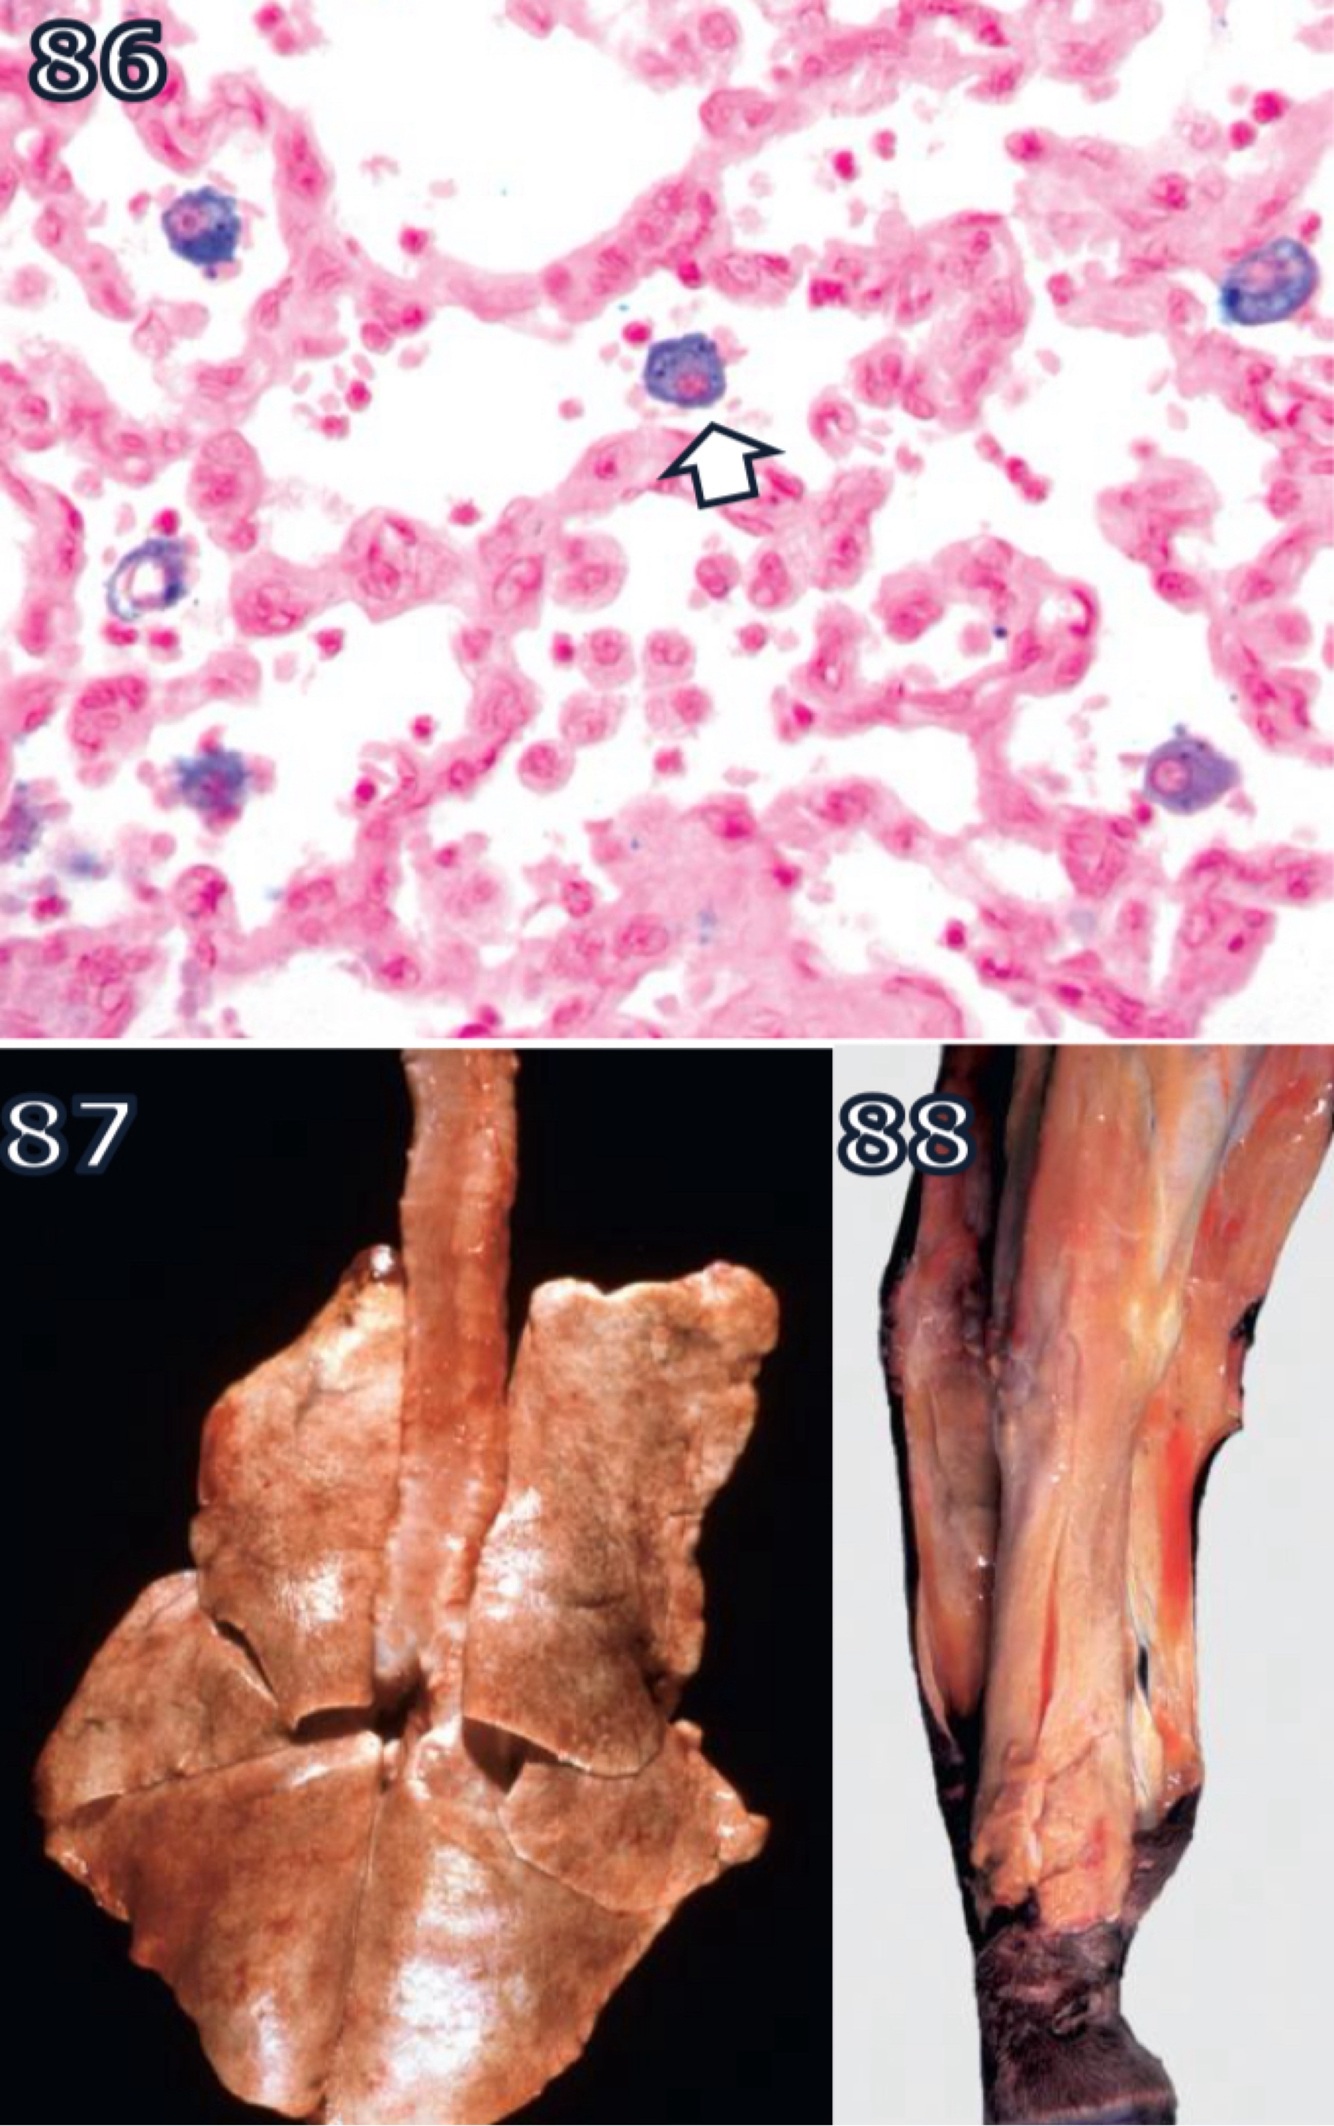

prasites infecting or consuming RBCs liberate heme during proteolysis of Hgb

free heme is toxic but parasites have evolved to aggregate it into heme dimers

accounts for blacking of migration tracts by juvenile liver flukes in ruminants + for black speckling of lungs in macaques infested w/ lung mite

released Hgb imparts transparent pink tinge to plasma/serum

kidneys = IV Hgb passes throughglom. capillaries into urinary filtrate (hemoglobinuria) w/ formation of Hgb casts in renal tubules + reddisch discoloration of ruine

- turns color of renal parecnhyma from dark red to gunmetal blue

similar or browner discoloration of kidney + urine occurs with myogobinuria

- derived from injured skeletal m. fibers